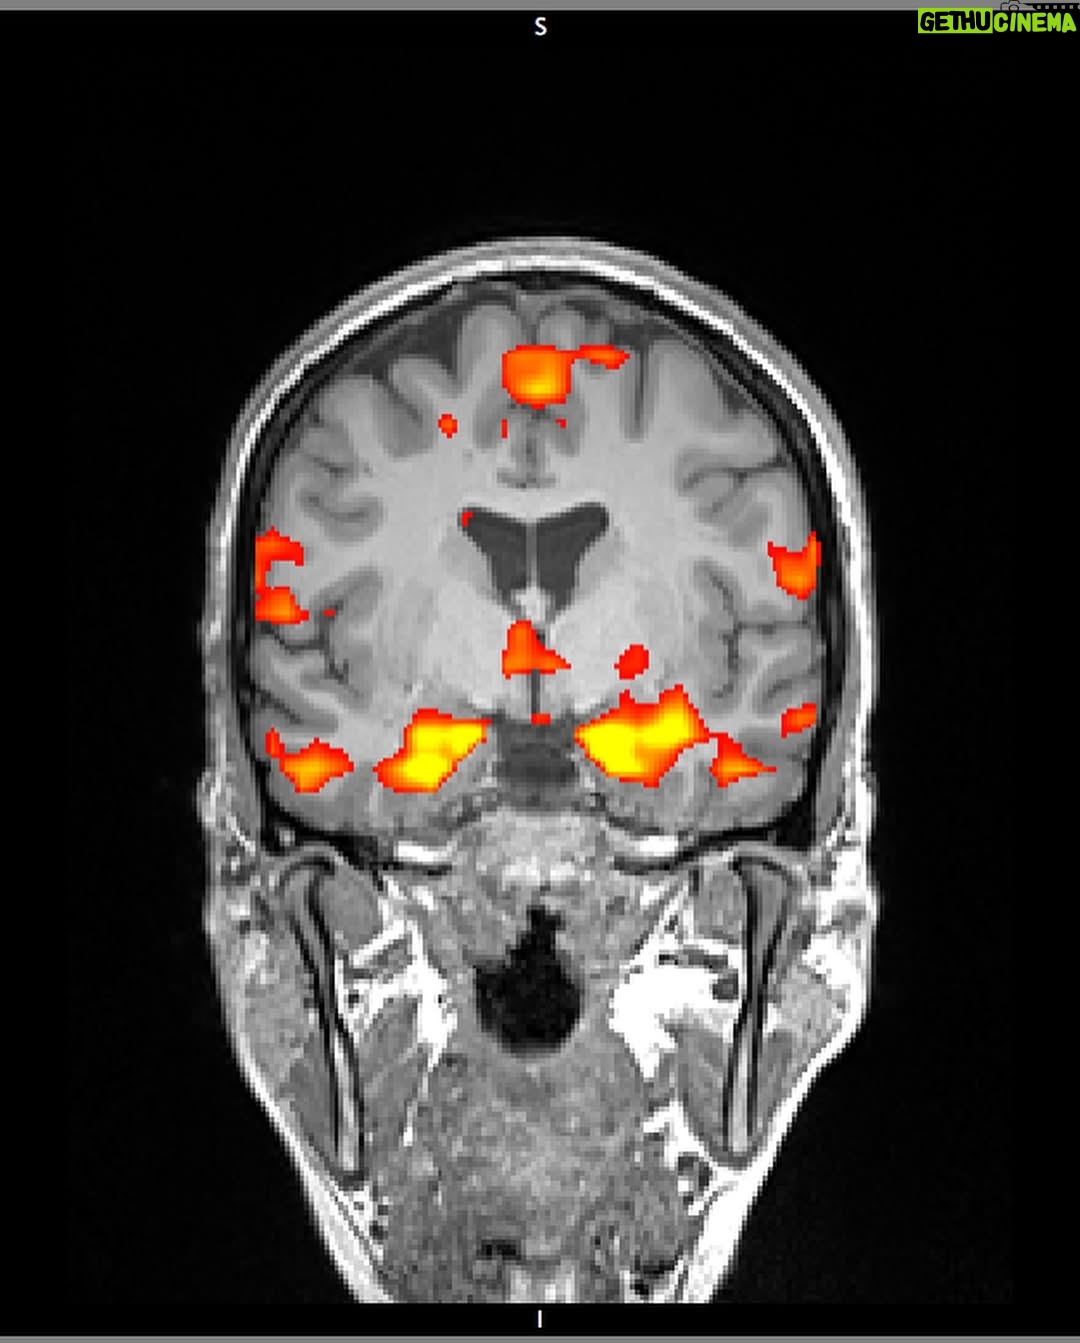

37.9K Likes – Sarah McDaniel Instagram

Caption : INNER LANDSCAPES full stylistic pilot in bio Director: @krotchy Cinematographer: @ty_mcgrath 1AC: @alex_dametto 2AC: @moshwarrior Gaffer: @liamvanderploeg Music: @bdbender VFX: @lucashrubizna Rotoscoping: @getcrspy Color: @sgllng Headpiece @lance.v.moore Special Thanks @northofnowfilms & @wfw_intl – We made this piece as part of a series that explores the inner landscapes of different artists and thought leaders. More to come 🤸🏻♀️Likes : 37922

37.9K Likes – Sarah McDaniel Instagram

Caption : INNER LANDSCAPES full stylistic pilot in bio Director: @krotchy Cinematographer: @ty_mcgrath 1AC: @alex_dametto 2AC: @moshwarrior Gaffer: @liamvanderploeg Music: @bdbender VFX: @lucashrubizna Rotoscoping: @getcrspy Color: @sgllng Headpiece @lance.v.moore Special Thanks @northofnowfilms & @wfw_intl – We made this piece as part of a series that explores the inner landscapes of different artists and thought leaders. More to come 🤸🏻♀️Likes : 37922

37.9K Likes – Sarah McDaniel Instagram

Caption : INNER LANDSCAPES full stylistic pilot in bio Director: @krotchy Cinematographer: @ty_mcgrath 1AC: @alex_dametto 2AC: @moshwarrior Gaffer: @liamvanderploeg Music: @bdbender VFX: @lucashrubizna Rotoscoping: @getcrspy Color: @sgllng Headpiece @lance.v.moore Special Thanks @northofnowfilms & @wfw_intl – We made this piece as part of a series that explores the inner landscapes of different artists and thought leaders. More to come 🤸🏻♀️Likes : 37922

37.9K Likes – Sarah McDaniel Instagram

Caption : INNER LANDSCAPES full stylistic pilot in bio Director: @krotchy Cinematographer: @ty_mcgrath 1AC: @alex_dametto 2AC: @moshwarrior Gaffer: @liamvanderploeg Music: @bdbender VFX: @lucashrubizna Rotoscoping: @getcrspy Color: @sgllng Headpiece @lance.v.moore Special Thanks @northofnowfilms & @wfw_intl – We made this piece as part of a series that explores the inner landscapes of different artists and thought leaders. More to come 🤸🏻♀️Likes : 37922

37.9K Likes – Sarah McDaniel Instagram

Caption : INNER LANDSCAPES full stylistic pilot in bio Director: @krotchy Cinematographer: @ty_mcgrath 1AC: @alex_dametto 2AC: @moshwarrior Gaffer: @liamvanderploeg Music: @bdbender VFX: @lucashrubizna Rotoscoping: @getcrspy Color: @sgllng Headpiece @lance.v.moore Special Thanks @northofnowfilms & @wfw_intl – We made this piece as part of a series that explores the inner landscapes of different artists and thought leaders. More to come 🤸🏻♀️Likes : 37922

37.9K Likes – Sarah McDaniel Instagram

Caption : INNER LANDSCAPES full stylistic pilot in bio Director: @krotchy Cinematographer: @ty_mcgrath 1AC: @alex_dametto 2AC: @moshwarrior Gaffer: @liamvanderploeg Music: @bdbender VFX: @lucashrubizna Rotoscoping: @getcrspy Color: @sgllng Headpiece @lance.v.moore Special Thanks @northofnowfilms & @wfw_intl – We made this piece as part of a series that explores the inner landscapes of different artists and thought leaders. More to come 🤸🏻♀️Likes : 37922